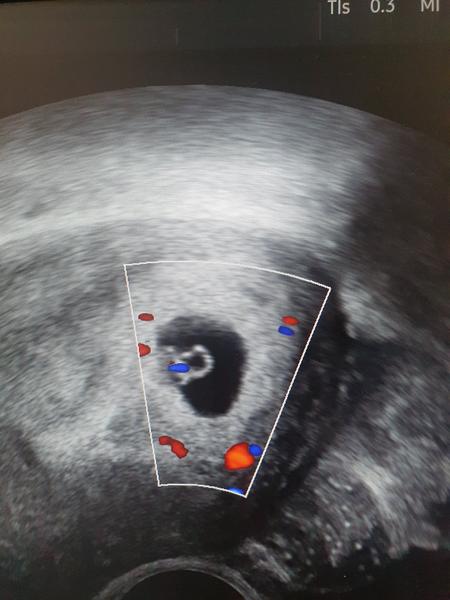

@azby Me tekly slzy na prvnim utz s dcerou. Na screeningu to bylo takove dojeti, ale neplakala jsem. Celou dobu jsem si myslela, ze to bude kluk. Ale nechtela se ukazat. Az na 2. screningu. A kdyz nam rekli, ze to bude holka, tak jsem bulela 😍 No a porod.....jak vylezla, tak ja i pritel total srastnej hysterak 😍 Uz aby byl ct a utz. Nemuzu se dockat. Akorat pritel nemuze se mnou 😔 A to se dozvime, jestli tam je jedno nebo dve 🙈

@lucipi Jejda, moc na tebe myslim. A neboj, muze to byt stale ok 🙏 Mohl to byt jen hematom. Ja myslim, ze v 6.tt to je normal, ze nemusi byt videt mimco ani srdicko. Taky jsem na to zitra pripravena. Ze treba za tyden to bude ok. Ale urcite volej do caru. Myslim, ze te pro jistotu i poslou na krev. Drzim palce, at je vse ok 🙏